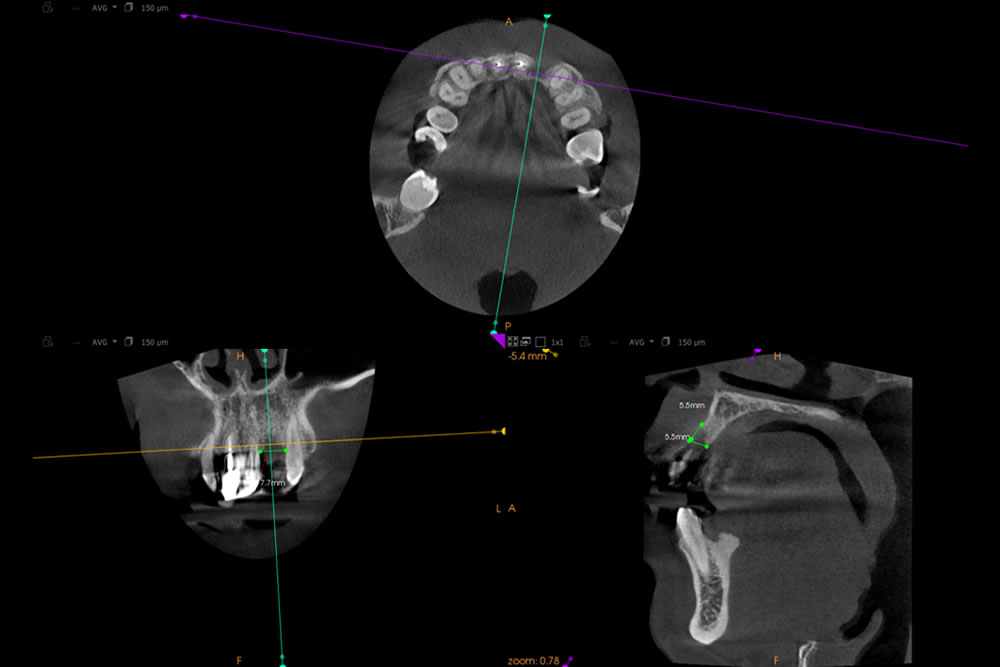

CT精密検査・シミュレーションの実施

インプラントが適切に行えるかを判断するため、精密検査やシミュレーションなどを実施しました。

シミュレーション

インプラントのネジ部分が露出しないようにしなければなりません。広範囲に骨を作ることができるのか、人工的に作った骨は長期的に信頼できるものか(溶けてなくなってしまわないか)など不安・懸念点がありました。

上記の問題点に加え、骨を作る量が多いので治療期間も非常に長くなることを患者様へお伝えしました。相談の結果、インプラントができないわけではありませんでしたが、数多くの困難な点、術後の不安定性などを総合的に考慮し、ブリッジで咬み合わせを回復することになりました。